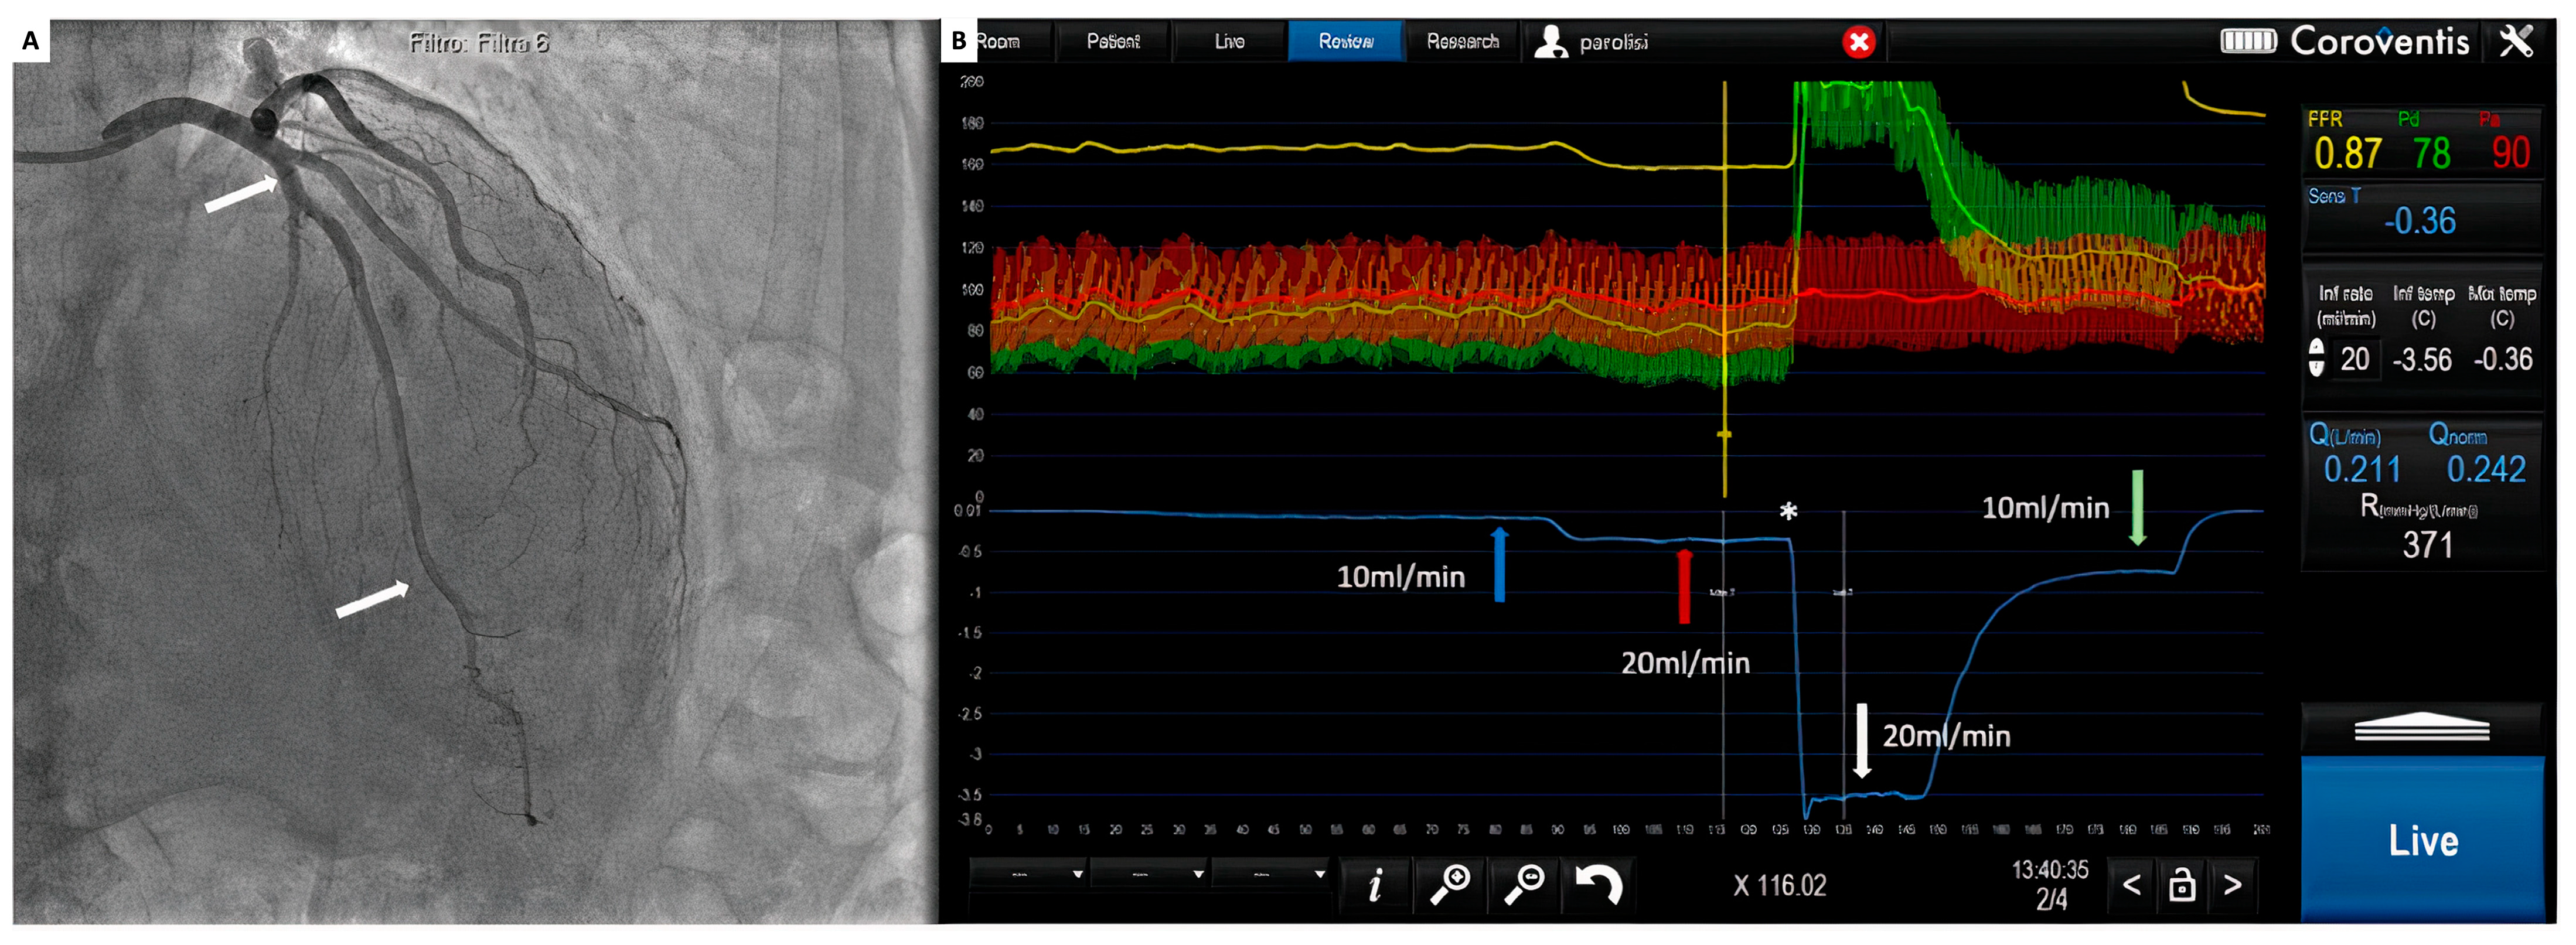

All signals are instantaneously recorded by a dedicated software (Coroflow® v3.0 Coroventis, Uppsala, Sweden), which can measure all pressure parameters, fractional flow reserve as well as absolute blood flow in mL/min and microvascular resistance in mmHg/L/min or wood units (WU) (Figure 5).

Figure 5.

(A) Coronary angiogram. White arrows: tip of the infusion microcatheter at the proximal part of the LAD and pressure–temperature wire at the distal part; (B) coroventis during continuous thermodilution. Blue arrow: temperature during infusion at 10 mL/min; red arrow temperature during infusion at 20 mL/min; *: pressure wire pull back; white arrow: temperature of the saline in the infusion microcatheter; green arrow: temperature during 10 mL/min.

Moreover, continuous thermodilution with infusion of saline at the low rate of 10/mL allows for the assessment of CFR (CFRabs) and microvascular resistance reserve (MRR). CFRabs is calculated by dividing Q during maximal hyperemia (Qh) and Q at rest (Qr):

Cardiac catheterization and FFR measurement can be performed as usual by either radial or femoral access. Guiding catheters and a pressure/temperature wire (Pressure wire X™, Abbott, Saint Paul, MN, USA) can be manipulated as a regular practice. After the intracoronary administration of 200 micrograms of nitroglycerin and proper equalization of pressures, the pressure wire can be advanced into the coronary artery. A dedicated monorail infusion catheter (Rayflow™, Hexacath, Paris, France) can be advanced over the pressure wire and positioned with its tip at the proximal part of the coronary artery [70]. This infusion catheter (2.5 French) consists of a 25 cm long rapid exchange inner monorail lumen for the 0.014″ wire, and it is equipped with four infusion holes guaranteeing rapid and complete mixing of saline with blood in the coronary artery. In addition, the infusion catheter has two inner side holes, which allow the recording of the temperature of saline at the site where it enters the coronary artery. Before saline infusion starts, the temperature is calibrated, and body temperature is set to “zero” (reference temperature); thereafter, all changes in temperature are related to this reference temperature (Figure 5). During the measurement, the pressure–temperature sensor of the pressure wire is positioned in the distal part of the coronary artery. Then, saline infusion is started at the rate of 10 to 20 mL/min, inducing maximal hyperemia within 10–20 s. After obtaining a steady state, the temperature of the completely mixed blood and saline (T) is measured in the distal coronary artery; the pressure/temperature wire is pulled back into the tip of the infusion catheter to measure the saline temperature (Ti) [71].